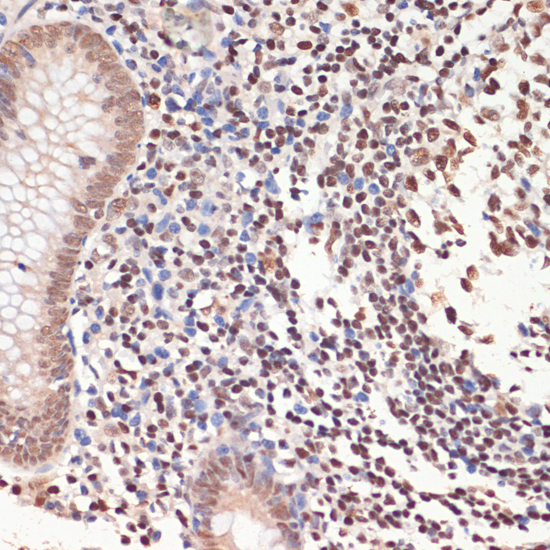

Facts about Poly [ADP-ribose] polymerase 1.

| Gene Name: | PARP1 |